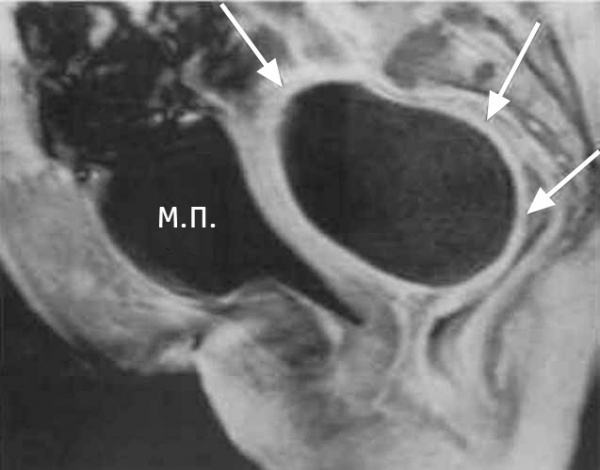

КТ органов малого таза. На снимке: абсцесс, отграниченный стенкой (А), прямая кишка (R), матка (U), мочевой пузырь (B)